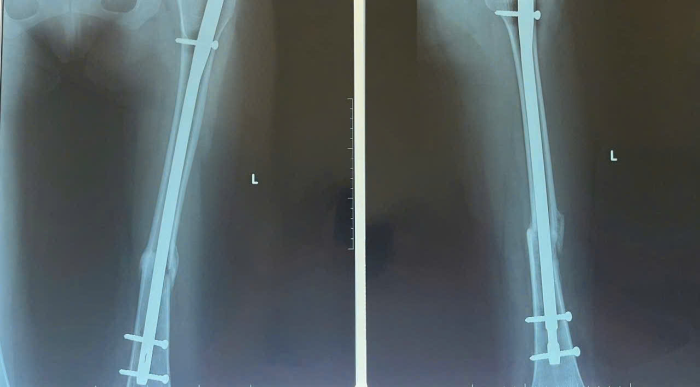

Thêm một trường hợp là bệnh nhân nữ P.L.P, 17 tuổi, sau 3 tháng được phẫu thuật bằng kỹ thuật đóng đinh nội tủy tại bệnh viện, vào ngày tái khám, ghi nhận bệnh nhân đã phục hồi tốt chức năng vận động so với trước, có thể đi lại mà không cần nạng và thực hiện được các sinh hoạt cá nhân cũng như công việc bình thường, kết quả chụp X-quang cho thấy xương đã liền tốt.

Hình ảnh X –quang xương đùi nữ bệnh nhân sau phẫu thuật 3 tháng